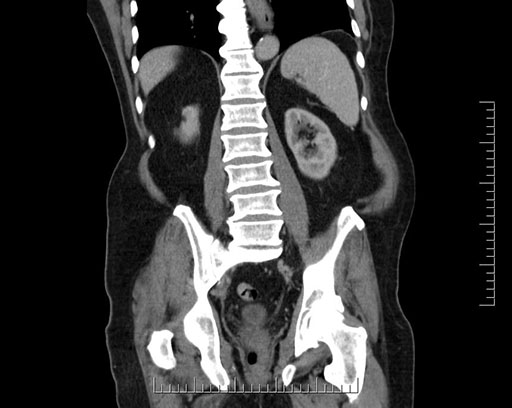

Axial - stented